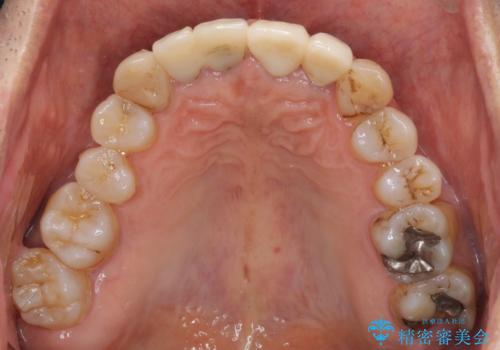

前歯のセラミッククラウンを装着したばかりであったので、根管治療のためにクラウンを壊さなければならないことを残念に思っていらっしゃいました。

しかし、根管治療後はすぐに痛みがひき、治療を受けられて良かったとのことでした。